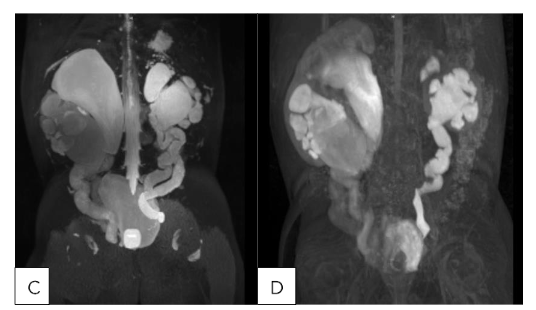

(A,B) 24 month old male with SFU Grade 4 hydronephrosis with UPJ morphology without obstruction/decompensation and (C,D) 23 month old female with bilateral duplex collecting systems with persistent grade 4 hydronephrosis following surgical reconstruction. (A) T2 MIP: Right kidney SFU grade 4, Left kidney SFU grade 1. (B) T1 Gd-enhanced MIP: Renal transit time is 2 minutes 1 seconds on the left, which is normal. Renal transit time is 1 minutes 47 seconds on the right, which is normal. (C): T2 MIP: Duplicated left kidney with cystic dysplasia of the upper left moiety and SFU grade 4 of the lower left moiety, Duplicated right kidney with SFU grade 4 of both upper and lower moieties, Tortuous ureters. (D) T1 Gd-enhanced MIP: Unit Patlak differential renal function is 56.9% on the lower left moiety and 43.1% on the upper left moiety. Renal transit time is 3 minutes 45 seconds on the left lower pole, which is nonobstructive. The left upper pole demonstrates trace contrast excretion. The equivocal range of the renal transit time of the right upper and lower pole is most likely related to capacious system. It does not appear to be high-grade obstruction.